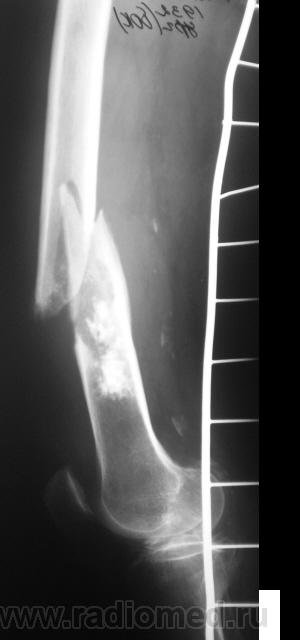

Ну, и, после "репозиции".

н\3 бедра со смещением по длине и ширине. Отломки находятся под углом открытым кпереди прим. в 10-15 град.

После репозиции дистальный отломок смещён латерально на ширину кортикального слоя.

А не создается-ли впечатления, что представленный перелом патологический? Первый снимок произведен через час после травмы.

костных структур в проекции прелома, то действительно это патологический перелом. Честно не сразу обратил внимание.

Что это - не скажу (под рукой нет литературы). Но. 1.Процесс опухолевый - в средней части, по заднему контуру отмечается вздутие кости. 2.Относительно длительно текущий - вздутие достаточно протяженное. 3.Пока еще относительно доброкачественный - кортикальный слой созранен. 4. Многоузловой (мультифокальный) - не менее 3-х узлов/фокусов. В зависимости от возраста/пола/анамнеза вполне может быть метастатическим. 5.Перелом все-таки патологический - линия перелома проходит через верхнюю часть патологического субстрата.

Это может оказаться и безобидным обызвествлением костного мозга после инфаркта, хондромой или хондросаркомой. - Уроки Татьяны Валентиновны. Но вздутия не вижу - его в боковой проекции симулирует третий фрагмент в месте перелома. Ну а метастаз - маловероятен... Опять же - "горим" на сочетанной патологии...

Как по мне, так там наоборот, локальное (хотя и на достаточном протяжении) УТОЛЩЕНИЕ кортикального слоя по задней поверхности, хотя и в сочетании с умеренным вздутием.

Данная рентген-картина может быть характерна и для хондросаркомы.

Вот, и у меня зародилась такая подлая мысль о наличии "хондро", и даже очень вероятно хондросаркомы.